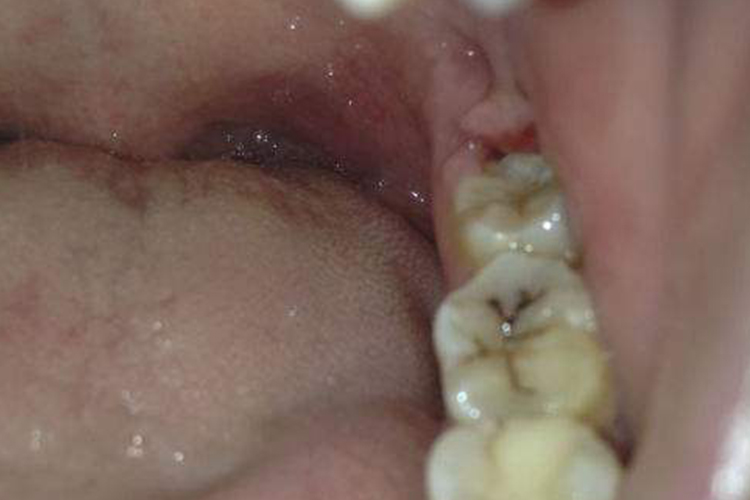

牙龈炎:牙龈炎患者由于局部组织水肿,龈缘变厚,不再紧贴牙面,龈乳头变的圆钝肥大,有时可呈球状增生,甚至可覆盖部分牙面。少数患者的牙龈炎症严重时,可出现龈缘糜烂或有肉芽增生。